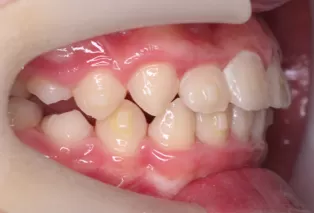

Photos intra-orales